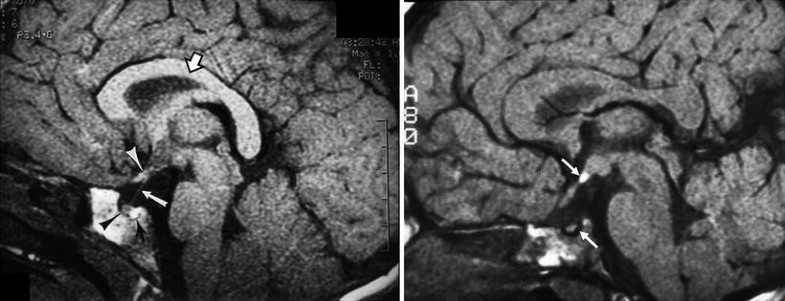

Posterior pituitary ectopia. (a) T1-weighted sagittal MR image demonstrating normal hyperintense signal of posterior pituitary gland (lower white arrow), normal pituitary infundibulum (lower white arrow), optic chiasm (upper white arrow). Open arrow denotes normal corpus callosum. (b) T1-weighted sagittal MR image demonstrating posterior pituitary ectopia (upper white arrow), which appears as abnormal focal area of increased signal intensity at tuber cinereum. Note absence of pituitary infundibulum and absence of normal posterior pituitary bright spot (lower white arrow). Upper white arrow denotes ectopic posterior pituitary gland. This child had a normal septum pellucidum and corpus callosum. Used with permission, from Brodsky and Glasier [58]. Copyright 1993, American Medical Association.

The finding of an absent pituitary infundibulum with no orthotopic or heterotopic bright spot corresponding to the posterior pituitary gland (Fig. 11.42) signifies loss of antidiuretic hormone secretion, which is associated with diabetes insipidus. When this finding is present, the anterior pituitary hormones are deficient as well.